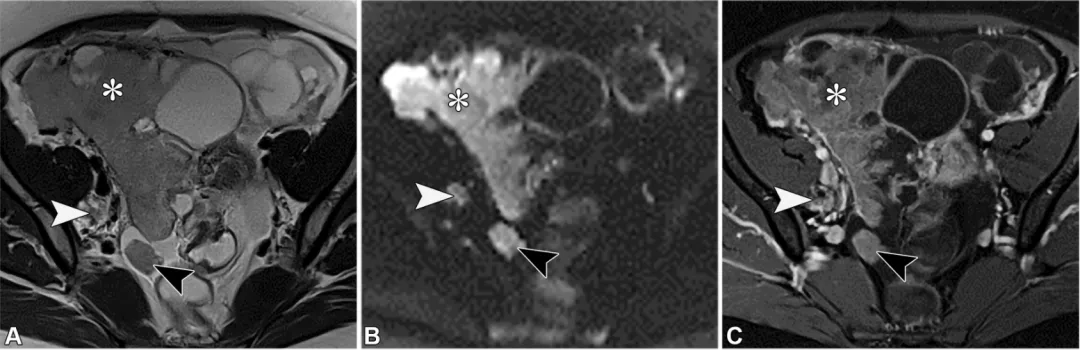

高级别浆液性卵巢癌(HGSOC)是最常见的侵袭性上皮肿瘤,也是总体上最常见的卵巢癌(36)。它通常发生在绝经后女性中,且与CA-125水平升高相关。高级别浆液性卵巢癌的一个风险因素是遗传性乳腺癌和卵巢癌综合征,该综合征主要由生殖系BRCA1/2突变引起,会导致发病年龄提前(54)。高级别浆液性卵巢癌常表现为双侧实性或囊性病变,伴有大体积的T2非低信号/弥散加权成像非低信号实性组织、腹膜种植灶、腹水,有时还有淋巴结肿大,这反映出由于缺乏早期症状且腹膜扩散迅速,其就诊时通常已处于晚期(图31)(36)。

图31. 一位52岁女性患者的高级别浆液性卵巢癌,该患者有腹痛、腹胀症状,且血清CA-125水平升高。轴位T2加权像(A)、高b值弥散加权像(B)和对比增强脂肪抑制T1加权像(C)显示双侧附件囊性病变,其中的实性组织(*)在T2加权像(A)上呈中等信号强度,在高b值弥散加权像(B)上呈高信号强度,且在对比增强像(C)上有强化。此外,还可见后陷凹的腹膜种植灶(黑色箭头)、腹水以及右侧盆腔淋巴结肿大(白色箭头)。